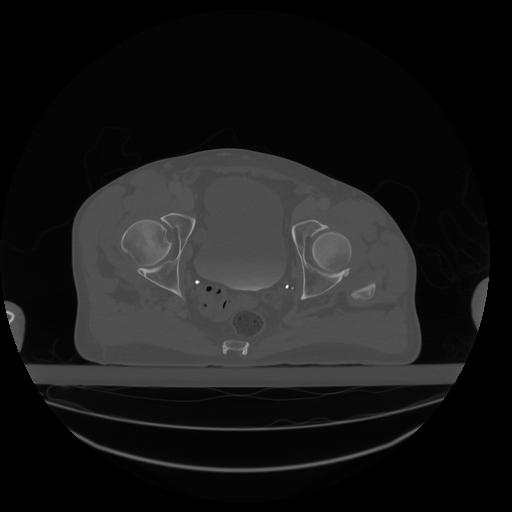

34 CUERPO,CE,Vol,1.0,CUERPO,,